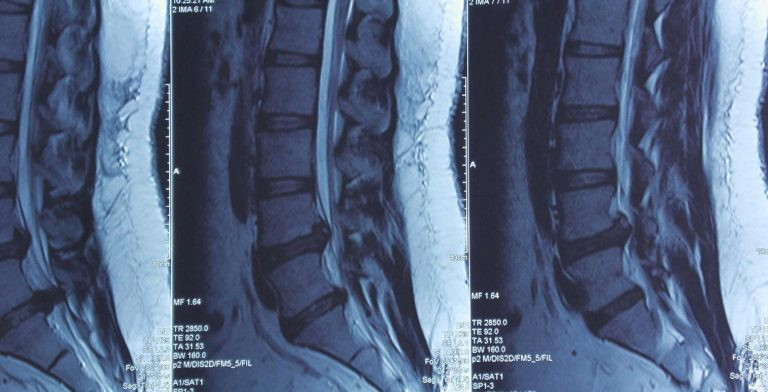

Hình ảnh MRI cho thấy tình trạng thoát vị đĩa đệm chèn ép nặng ống sống và rễ thần kinh. Ảnh: BVCC

Sau khi thăm khám, các bác sĩ tại Khoa Sọ Não Cột Sống 2 đã tiến hành chụp MRI và phát hiện một khối thoát vị lớn chèn ép nặng ống sống và rễ thần kinh, thủ phạm chính gây ra cơn đau đớn vùng lưng, mông đùi phải cho người bệnh. Ngay lập tức, êkip quyết định phẫu thuật nội soi lấy thoát vị đĩa đệm – một kỹ thuật xâm lấn tối thiểu, cho phép tiếp cận chính xác khối thoát vị mà vẫn bảo tồn tối đa các mô xung quanh.